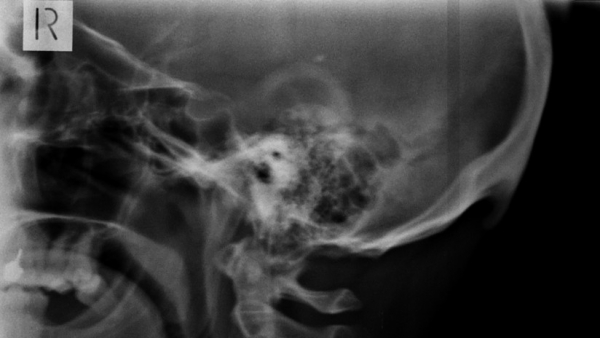

El uso continuado de teléfonos inteligentes está provocando un cambio en la forma del cráneo humano, afirman investigadores australianos. Se trata de un hueso en forma de pico, llamado protuberancia occipital externa, que aparece en la parte posterior de la cabeza, un poco por encima el cuello. Este puede sentirse al tacto y a veces incluso puede resultar visible en personas calvas.

Tras su descubrimiento, el científico decidió llevar a cabo unas investigaciones para determinar el alcance de la propagación de la anomalía. En 2016, lideró un estudio que analizó a 218 personas de entre 18 y 30 años de edad. El trabajo, publicado en la revista Journal of Anatomy, mostró que el 41 % de los participantes tenían en su cabeza 'picos' de más de 10 milímetros, mientras que en un 10 % de los examinados superaban los 20 milímetros.

En otra investigación, publicada en febrero de 2018 en la revista Nature, Shahar se centró en determinar la edad de las personas que contaban con ese tipo de formaciones. En el estudio participaron 1.200 individuos de entre 18 y 86 años, y el análisis concluyó que era "significativamente más probable" encontrar estas protuberancias entre los participantes de entre 18 y 30 años.

El científico señala a los dispositivos inteligentes como los responsables de la aparición de este abultamiento. Cuando nos inclinamos sobre las pantallas, los músculos del cuello se tensan para sostener la cabeza, cuyo peso aproximado es de 4,5 kilogramos. En el lugar donde aparece este 'pico' se concentra una gran presión muscular, y los especialistas creen que el cuerpo trata de adaptarse para aliviar esta presión creando nuevos huesos que ayuden a repartir el peso de la cabeza por una superficie mayor.